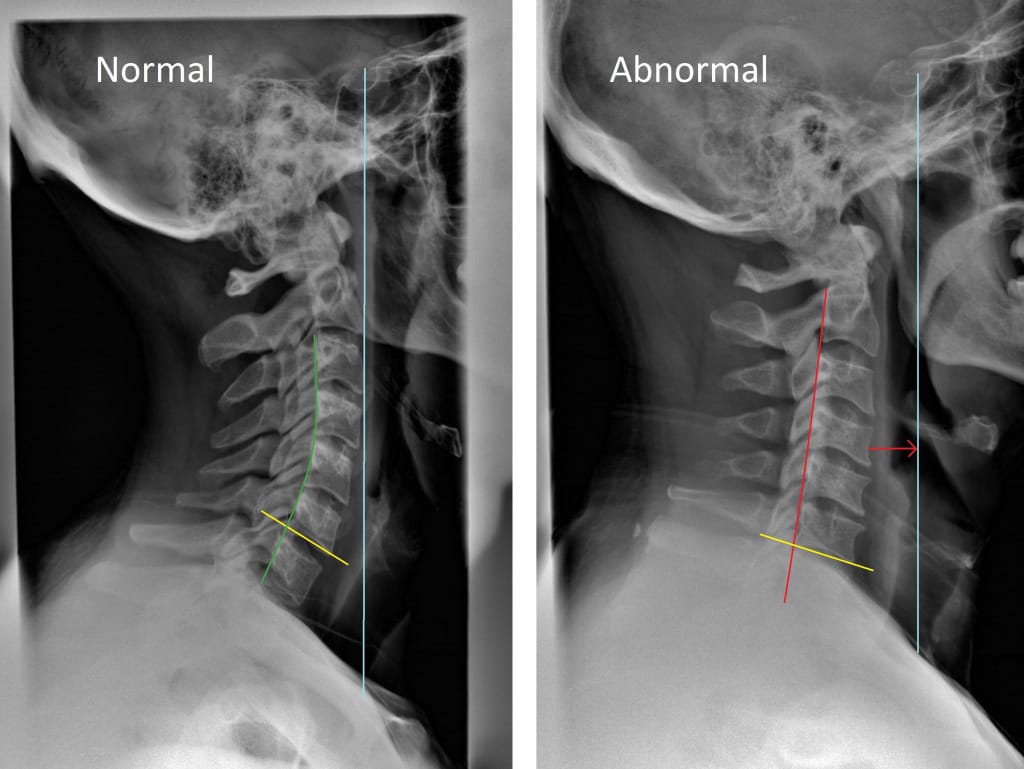

Neck and Shoulder Tension: Heavy Head?

Sitting At A Computer In today’s world, the majority of us have jobs that require hours of working at a computer, sitting at a desk, or attending meetings (more sitting!)….